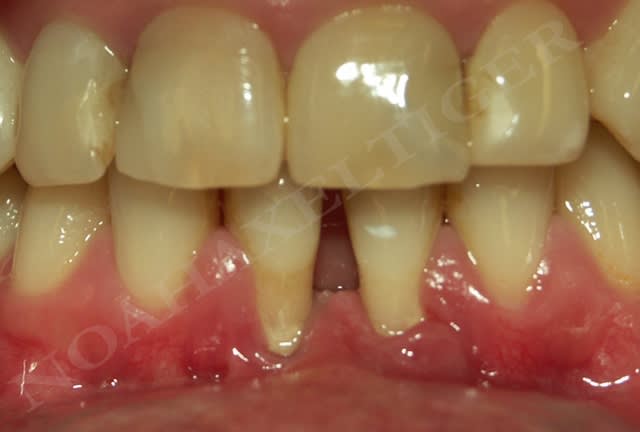

Dans le cas suivant, l'atteinte interproximale 31-41 n'autorise malheureusement aucune solution de recouvrement radiculaire :

Img 8511 llqbsh - Eugenol